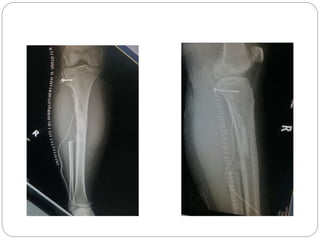

This document discusses 8 oncology cases. Case 1 involves a 40-year old female with right knee pain. Case 2 is a 28-year old male with a left subtrochantric fracture from a MVA who is now experiencing increasing left knee pain and swelling. Biopsy results showed high-grade osteosarcoma. Case 3 is a 30-year old female with breast cancer and bone metastases causing bilateral hip pain.